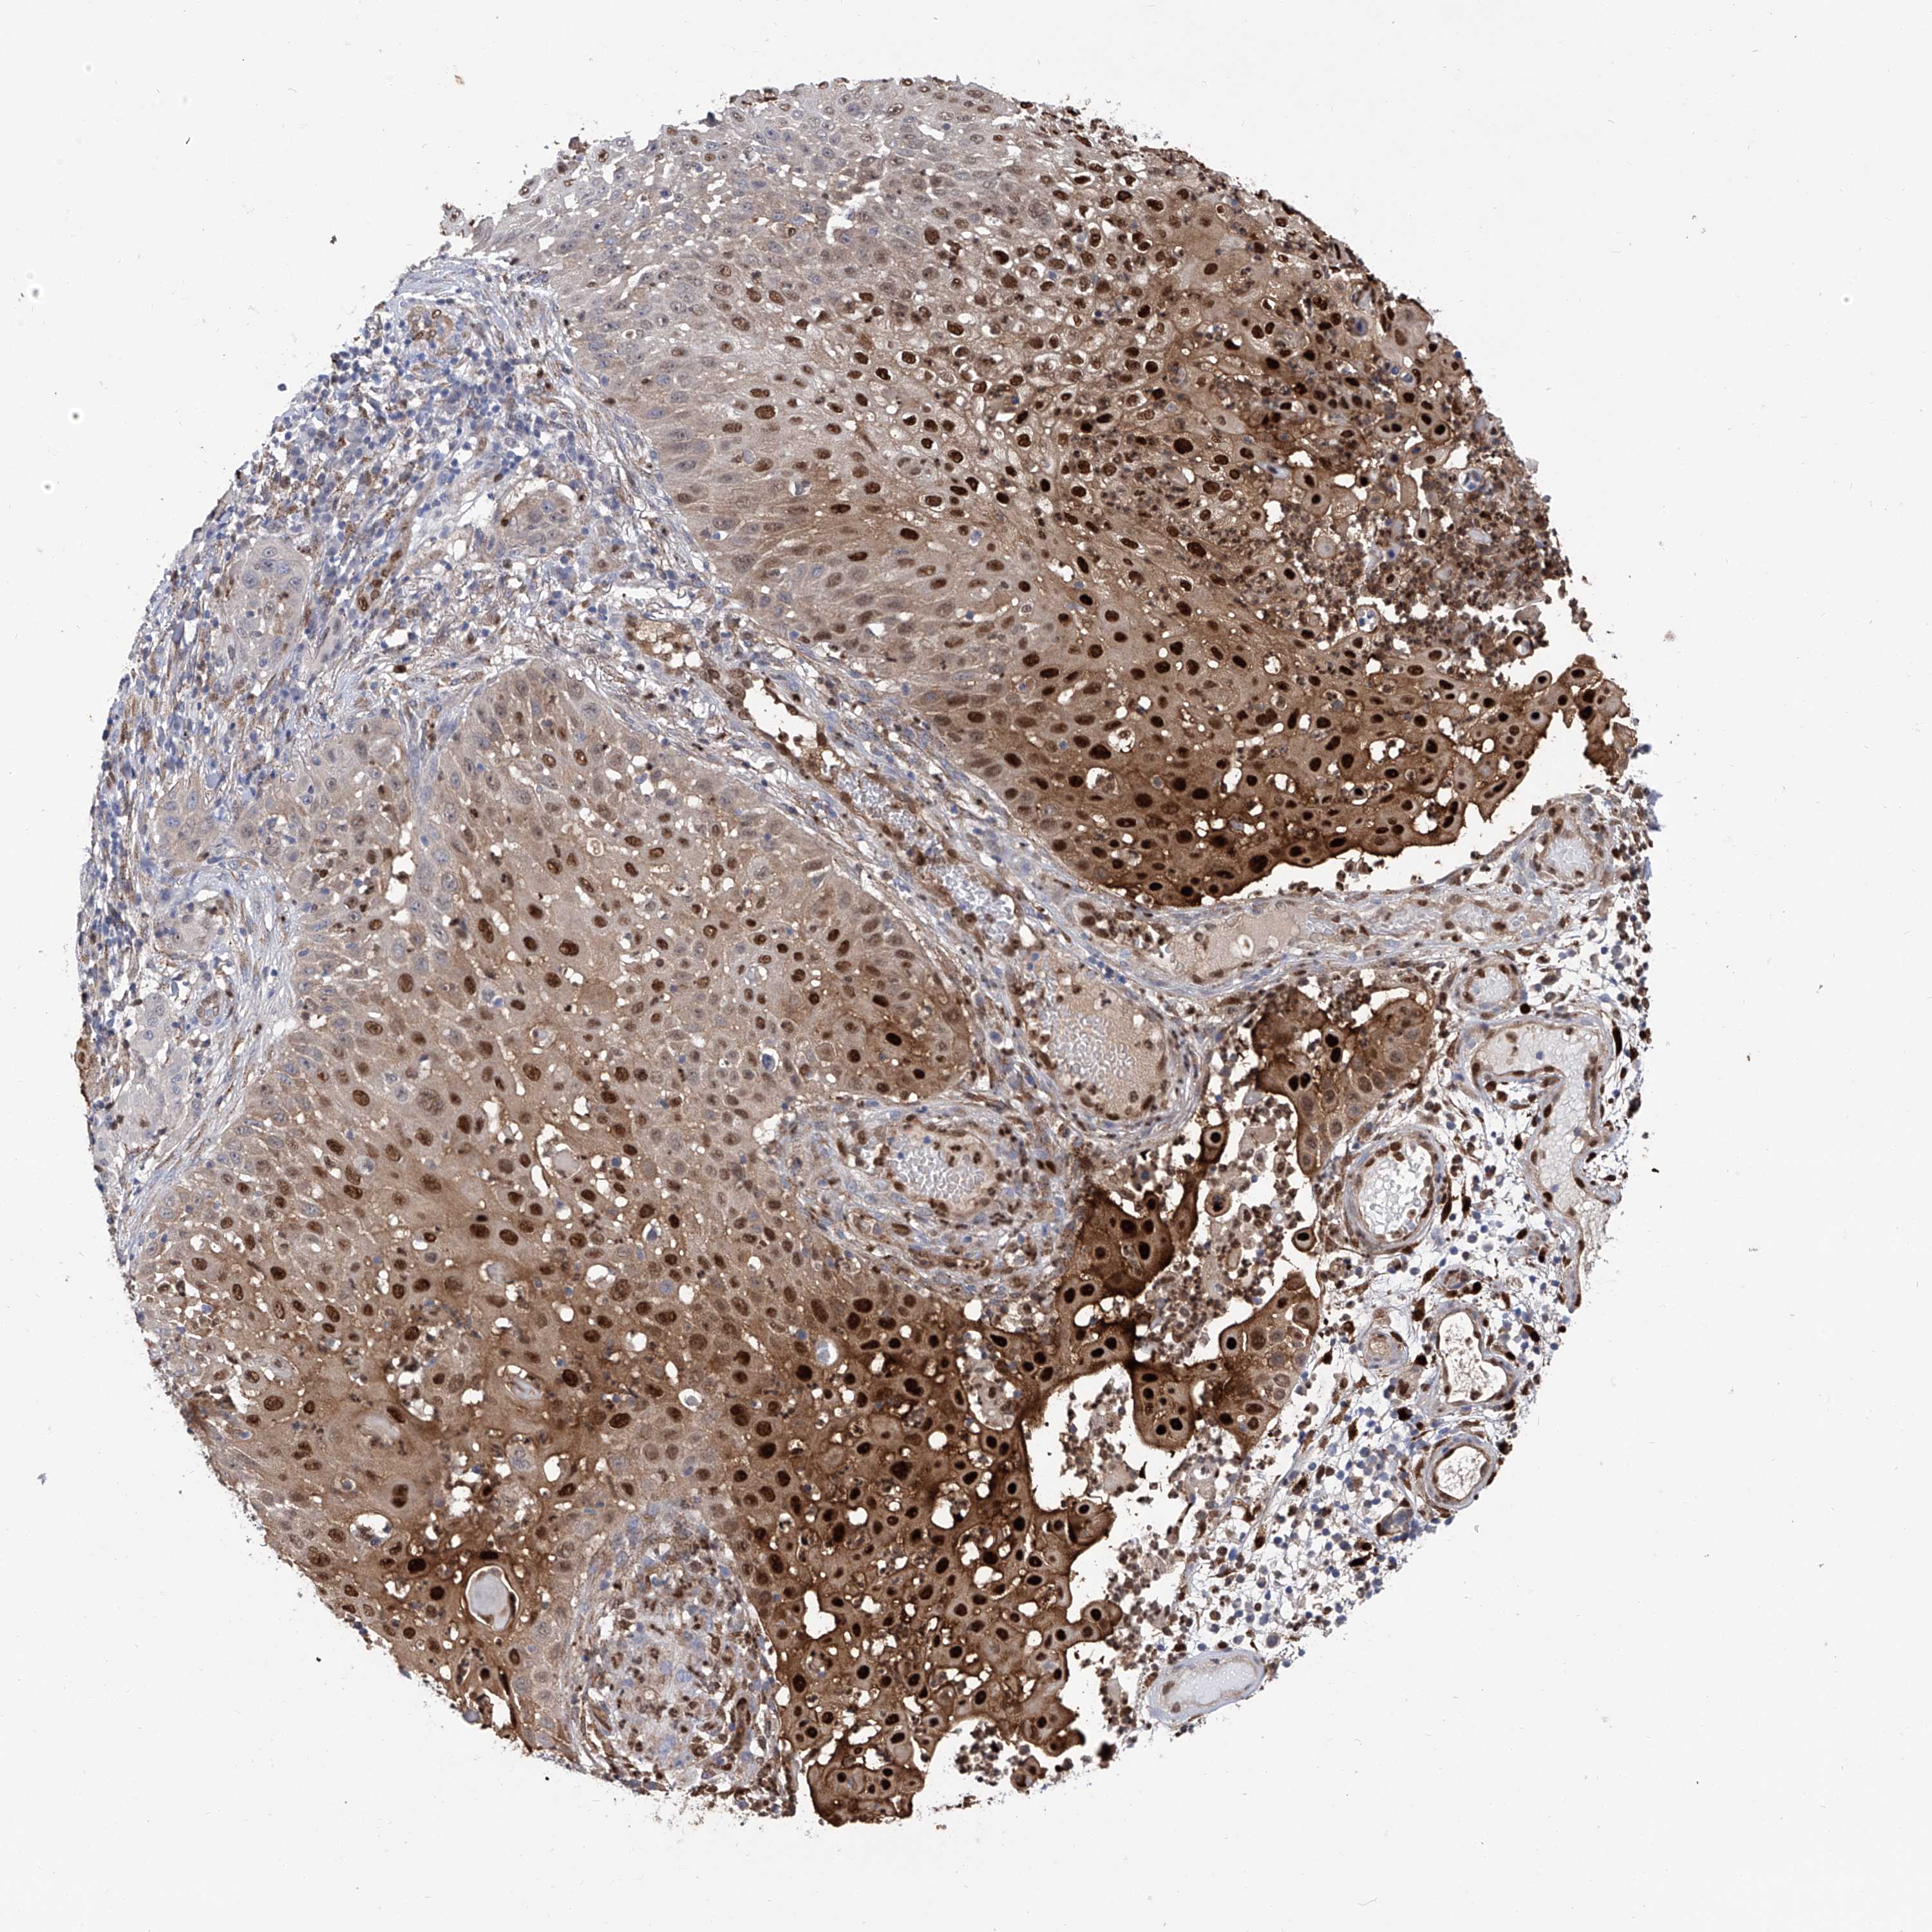

Basal cell and squamous cell cancer

SKIN CANCER - Protein expressioni

A mouse-over function shows sample information and annotation data. Click on an image to view it in a full screen mode. Samples can be filtered based on level of antibody staining by selecting one or several of the following categories: high, medium, low and not detected. The assay and annotation is described here.

Each image is clickable and will lead to virtual microscopy that enables deeper exploration of all samples and also displays staining intensity scores, fraction scores and subcellular localization as well as patient and tissue information for each sample.

Antibody HPA029619

Basal cell carcinoma

Squamous cell carcinoma, NOS